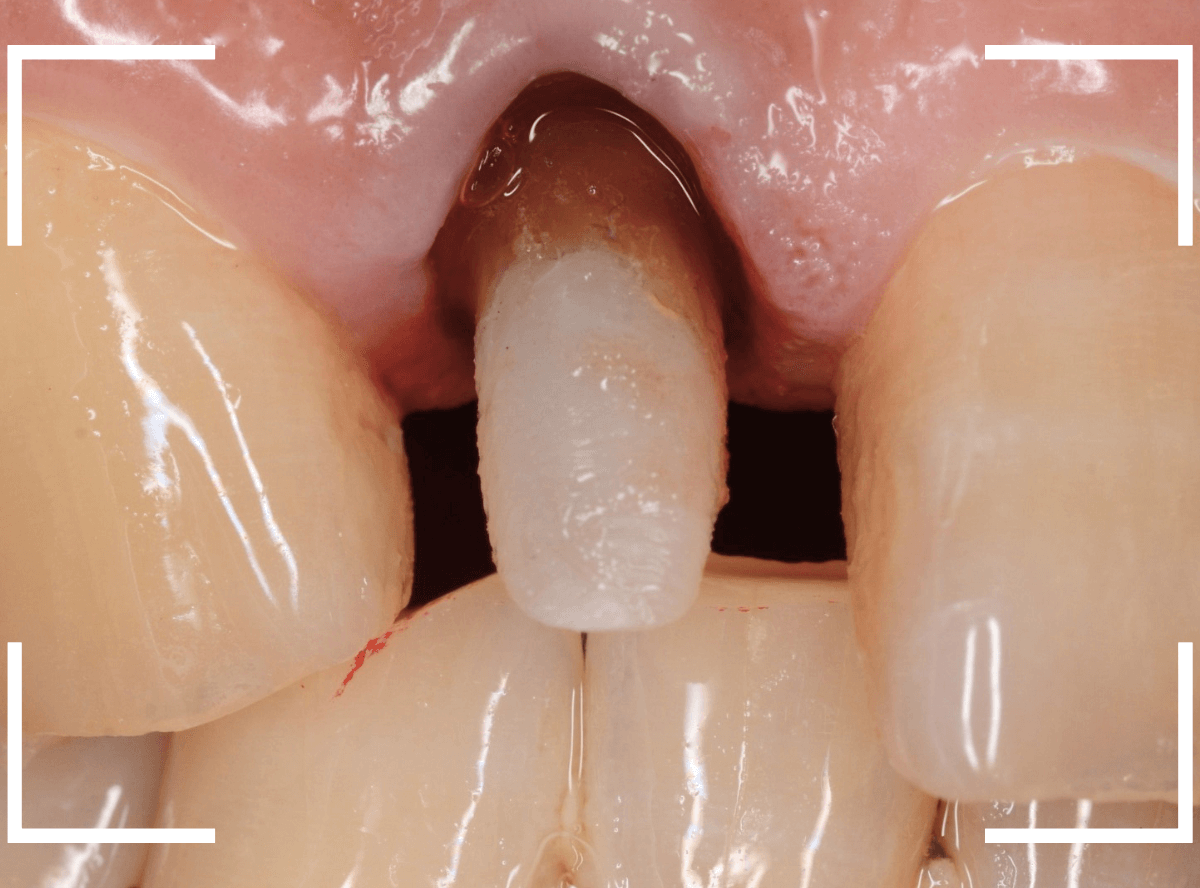

この形に合わせた仮歯を製作し、歯肉が落ち着くまでしばらく経過観察します。

痛みが引き、歯肉の形が整ってきたところで、型をとってさし歯を製作します。

今回は、ジルコニア・セラミックで製作する事になりました。

模型上で精密に制作します。

ジルコニア・セラミックは歯の内側や見えない部分にも一切金属を使用しないさし歯ですので、治療後の金属色で悩むこともありませんので、オススメです。

お口の中でsetしたところです。

お口の中に入った状態のビフォーアフターです。

見た目の印象も大きく変わったかと思います。

また、以前のさし歯に比べて、舌触りがとてもよくなったとの感想もいただきました。